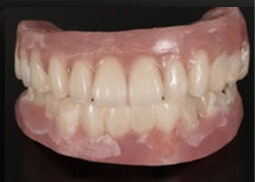

⑤ 美しい最終補綴

専属の歯科技工士により、芸術まで高められた最終補綴物を貴方に、心を込めて贈ります。これらのテクニックはほんの一部です。オールオン4は高度なインプラント技術を必要とする治療の1つです。後悔しない為にクリニック選びは慎重に行って下さい。

最終補綴1

最終補綴2

最終補綴3

最終補綴4

最終補綴5

最終補綴6